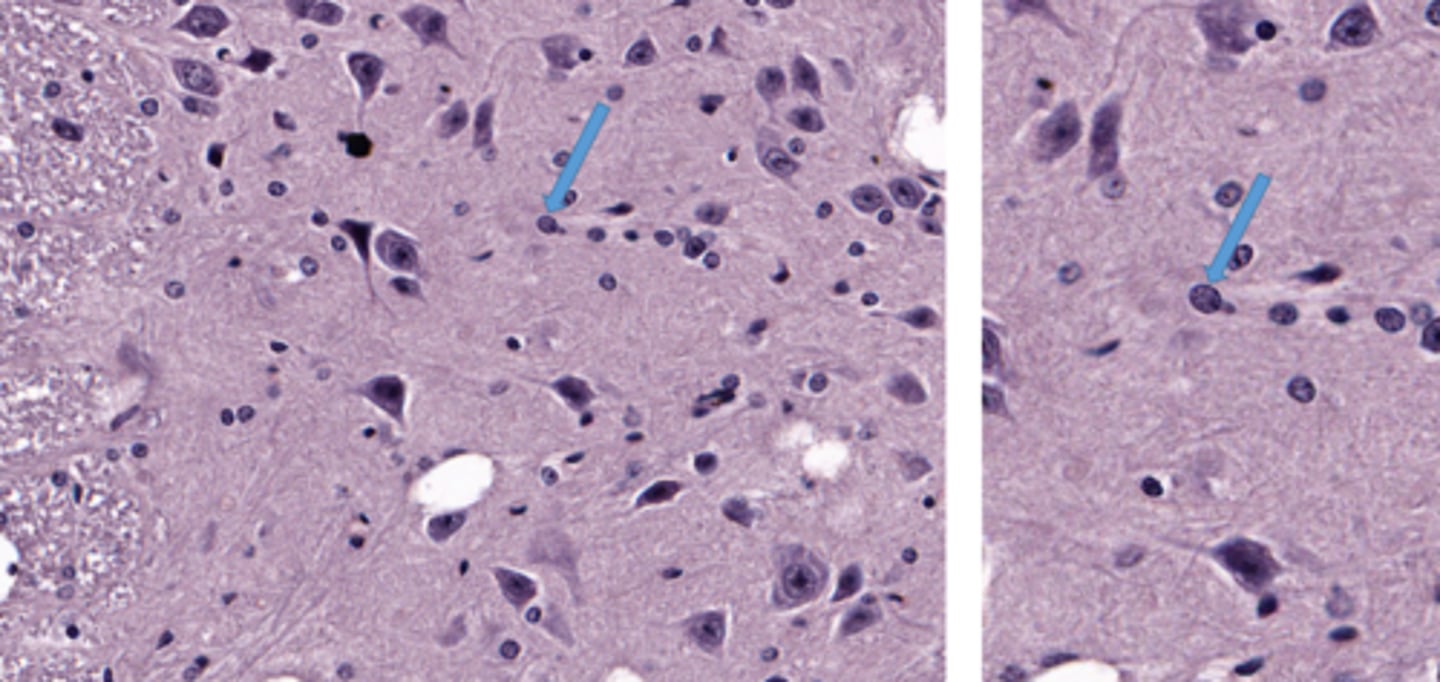

Identify this cell

purkinje cells in the brain

Identify the glial cell

oligodendrocyte

astrocyte

microglial cell

satellite cell

pyramidal cell